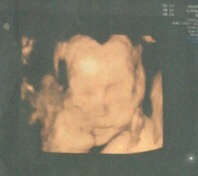

孕22周+2天

孕21周+3天

孕35周+1天